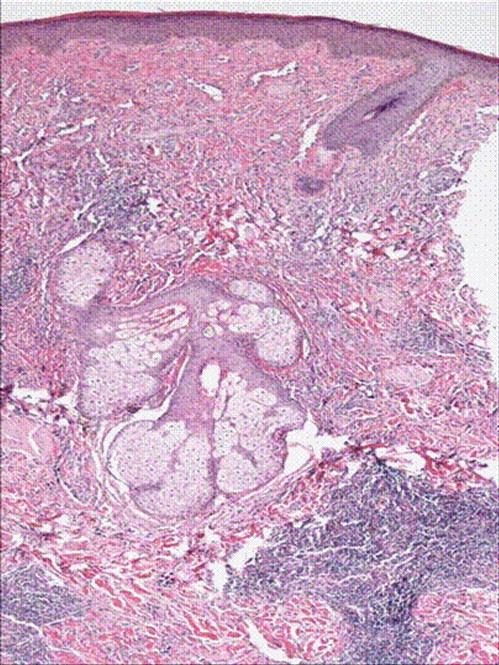

H& E stain of punch biopsy of the lesion from the cheek showing infilterating vascular tumor.

A 50 year old male with past medical history of diabetes, hypertension was diagnosed with angiosarcoma localized to the face (Figure 1 & Figure 2). The patient had baseline mild coagulopathy before start of chemotherapy most likely from the angiosarcoma. He received the first cycle of paclitaxel and bevacizumab but required hospitalization four days later for chest pain and acute coronary syndrome was ruled out. He then developed febrile neutropenia with an ANC of 0.0 and progressive pancytopenia. On day 9 of chemotherapy, the patient had a platelet count of 12 K/μ L with hemoglobin of 6.1gm/dl, hematocrit of 18% and WBC count of 3 k/μ l. The peripheral smear revealed many schistocytes, in addition elevated LDH 1112U/L, with an indirect bilirubin of 2.62 mg/dl, total bilirubin of 3.80mg/dl, and a haptoglobin of less than 10. His coagulopathy progressed with a PT of 17.3, PTT 65.3, fibrinogen degradation products (FDP) which were less than 10 on day 6 post chemo, were more than 40 on day 8 and his D-Dimers were 13.5 mg/l(Figure 5). ADAMTS13 level was drawn and though his creatinine and mental status remained normal, plasmapharesis was initiated with the presumptive diagnosis of thrombotic thrombocytopenic purpura (TTP).